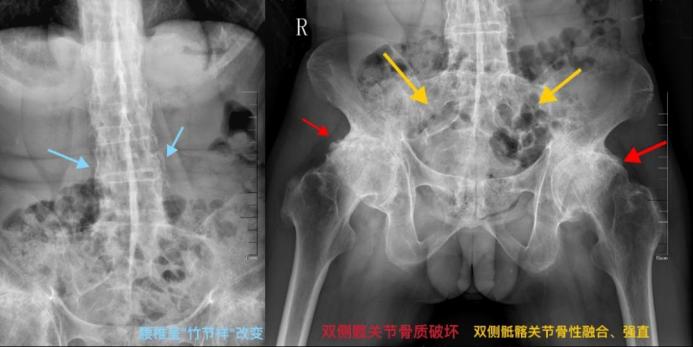

隨著病情發(fā)展,可能會(huì)導(dǎo)致脊柱、骶髂關(guān)節(jié)、髖關(guān)節(jié)等出現(xiàn)強(qiáng)直性的改變,嚴(yán)重者整個(gè)脊柱會(huì)像竹子般僵硬,甚至畸形、致殘,并可伴有不同程度的心、肺、眼、腎等多器官損害。發(fā)病時(shí),患者疼痛難耐,備受煎熬,并且該病會(huì)綿延一生,因此被稱為“不死的癌癥”。

強(qiáng)直性脊柱炎患者的脊柱呈“竹節(jié)樣”改變。

疾病通常從骶髂關(guān)節(jié)開(kāi)始,逐漸向上蔓延至腰椎、胸椎乃至頸椎。若不及時(shí)控制,長(zhǎng)期炎癥會(huì)導(dǎo)致韌帶骨化、脊柱融合,最終使脊柱如“竹節(jié)”般僵硬,喪失活動(dòng)度,形成駝背等畸形。